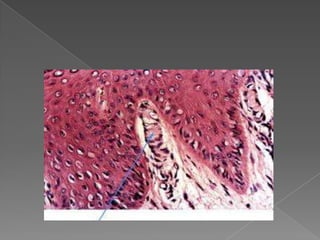

Detalhe da camada basal (1) e parabasal (2),

 Camada espinhosa - células poliédricas

Detalhe da camadabasal (1) e parabasal (2),